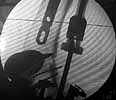

Well, finally i still performed antegrade nailing. After the distractor was applied, reduction of the recent fracture was obtained "automagically".

But the previous fracture resulted with some posterior displacment of the distal part, so antegrade nail would pass anteriorly, and retrograde nail, even a short one, would have penetrated anterior cortex proximally to the fracture. So perQ osteotomy was necessary to add some mobility at the level, and after that the nail was easily inserted to the distal fragment. The nail is solid, 13 mm, locking screws 6 mm. Locked statically.